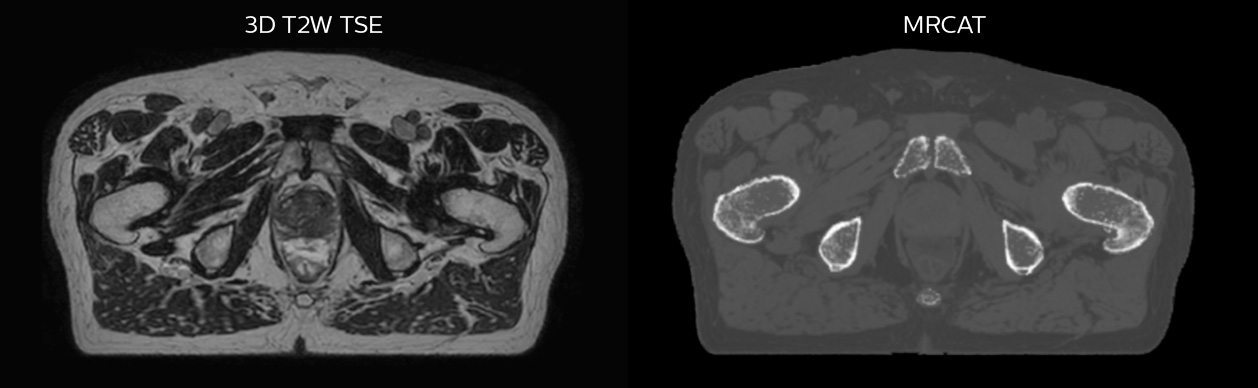

MR-only radiotherapy planning with MRCAT

Philips MRCAT (MR for Calculating ATtenuation) provides exceptional soft tissue contrast for target and OAR delineation, in addition to the Hounsfield units needed for dose calculations. This permits an MR-only radiotherapy planning workflow. Philips pioneered MR-only radiotherapy with the introduction of MRCAT Prostate, followed by the expansion to the whole pelvis with MRCAT Pelvis. This application can be used for a broad range of pelvic indications, including cancers in the prostate, rectum, bladder, anal canal and cervix. Next to MRCAT Pelvis, MRCAT Brain is available for radiotherapy planning of primary and metastatic soft-tissue tumors in the brain.

Dataset MRCAT image

Dose plans overlaid on CBCT image dataset (left) and on MRCAT image dataset (right).